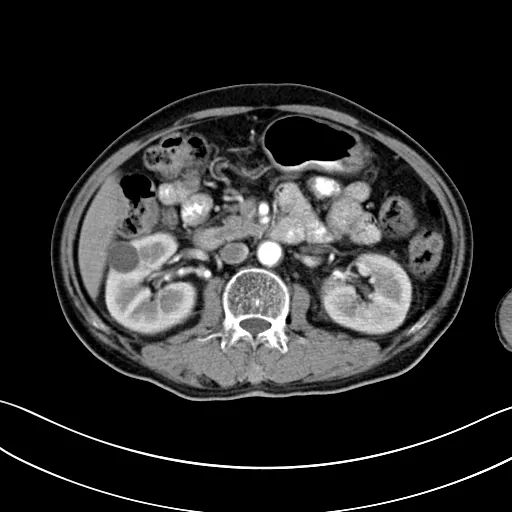

2019.05.09

自2017年做冷冻消融术后,安图叔叔两年多时间肿瘤不仅没有增长并多次检查没有复发迹象。安图叔叔认为,冷冻给他带来新的希望,又一次看到复大创造新的奇迹。